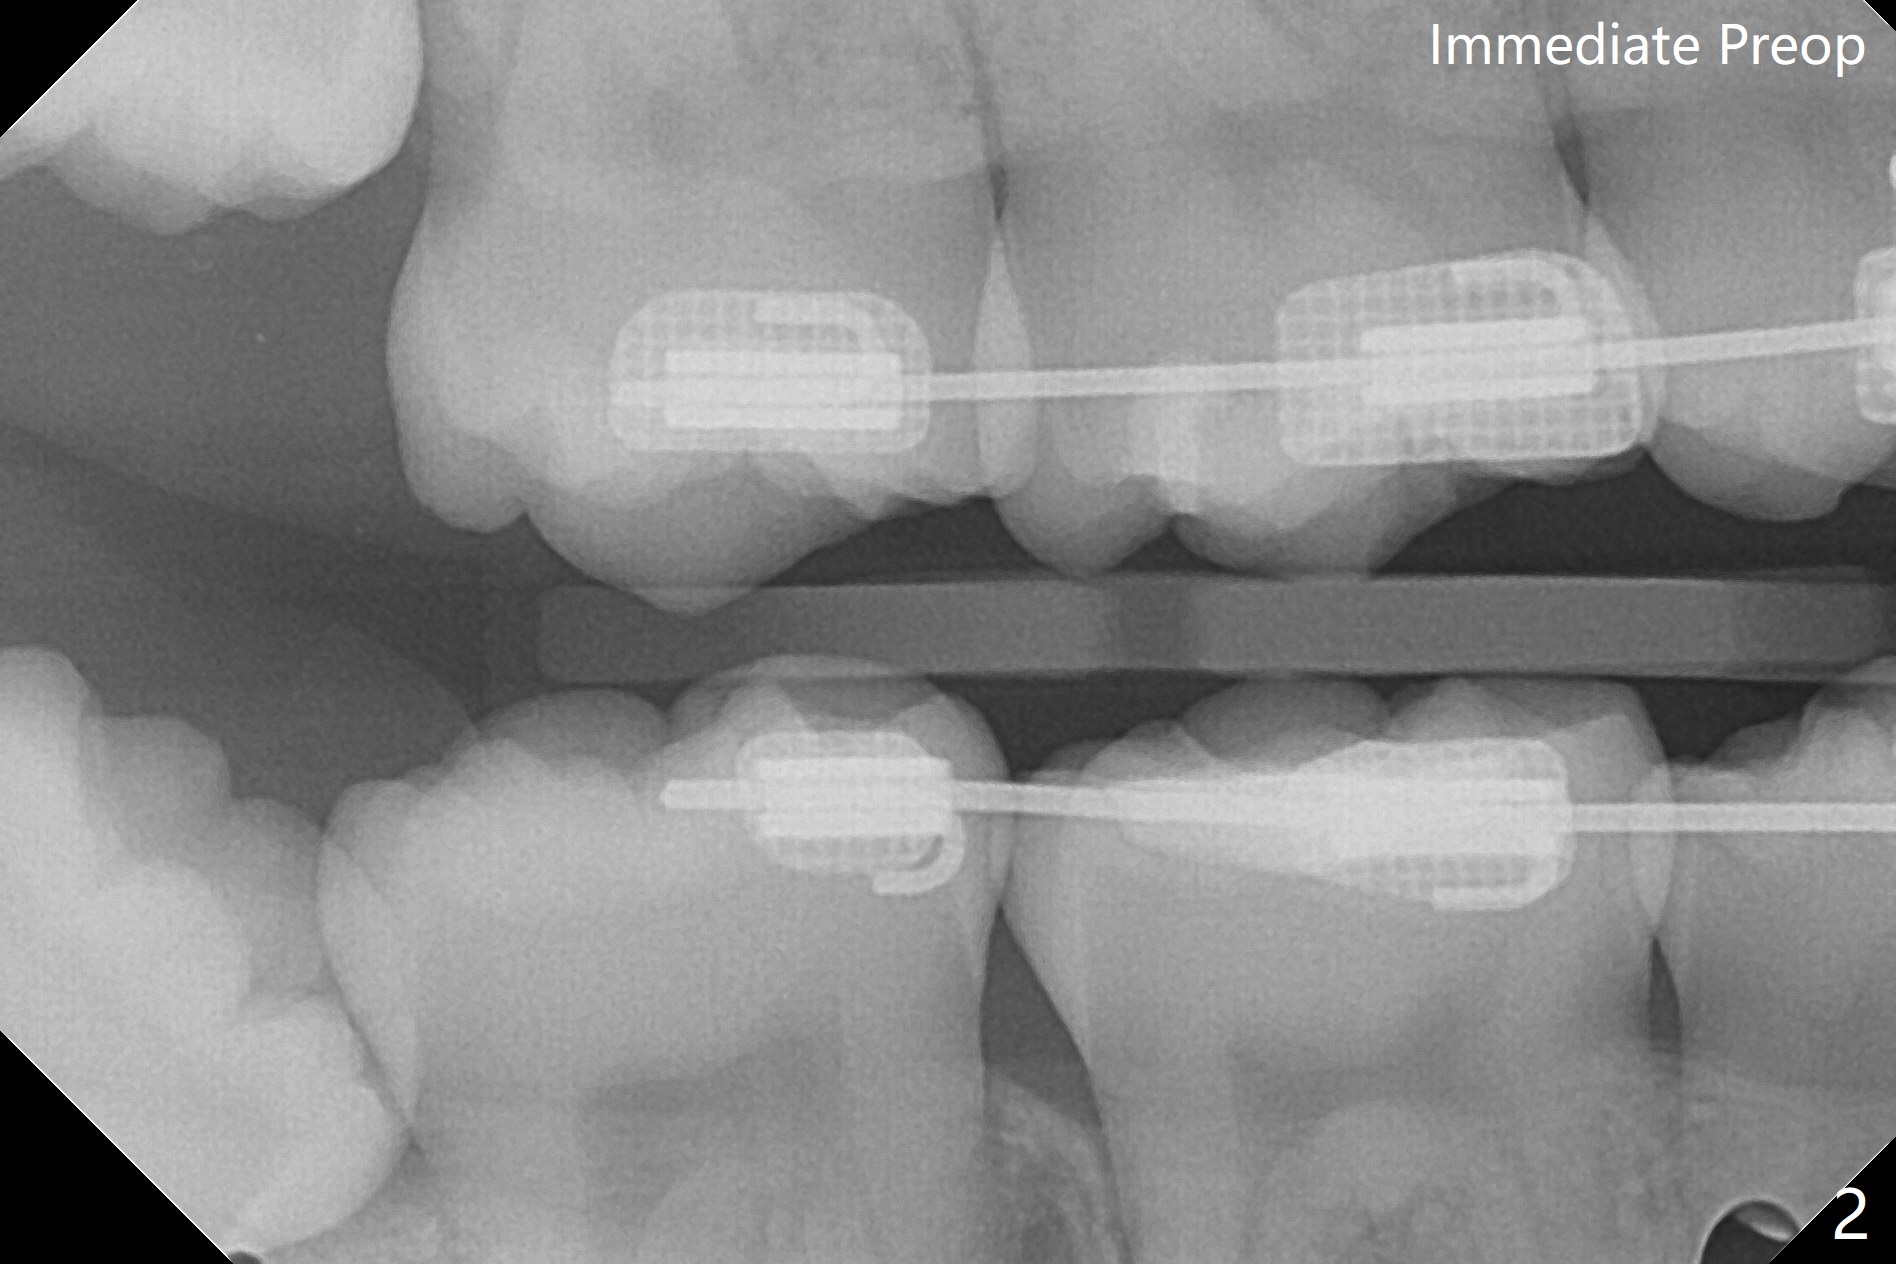

17岁女孩3年前拍摄全景片后拔除4个第一双尖牙(图一),在别的诊所进行矫正(图二,三),在局麻下拔除4个智齿,由于去骨,显得外斜嵴缺失(图四:箭头),放置胶原塞(防止干槽症),4-0含铬羊肠线缝合,预计外斜嵴6-12月能修复。